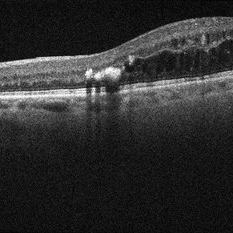

FA 40 Seconds - Large Hemorrhage With Macular Detachment Due to AMD

Nov 7 2019 by John S. King, MD

81-year-old white female with three day history of seeing a "dark blob" nasally OD; no blood thinners; vision was 20/100- J16 with 2+NSC OD; OCT (not shown) had large SRF that included the fovea and extended out temporally. Posterior segment showed a large amount of SRF in the macula with some SRH in the inferior portion of the macula, hemorrhagic PEDs temporally with some RPE scarring and SRH in the periphery. On the FA there is blockage by the SRH and SRPE heme; there is staining peripherally; there is a wave of leakage that extends out into the macula and pools into to subretinal space.

Photographer: Brandon Peter

Condition/keywords: retinal pigment epithelium, subretinal hemorrhage, wet age-related macular degeneration (wet AMD)